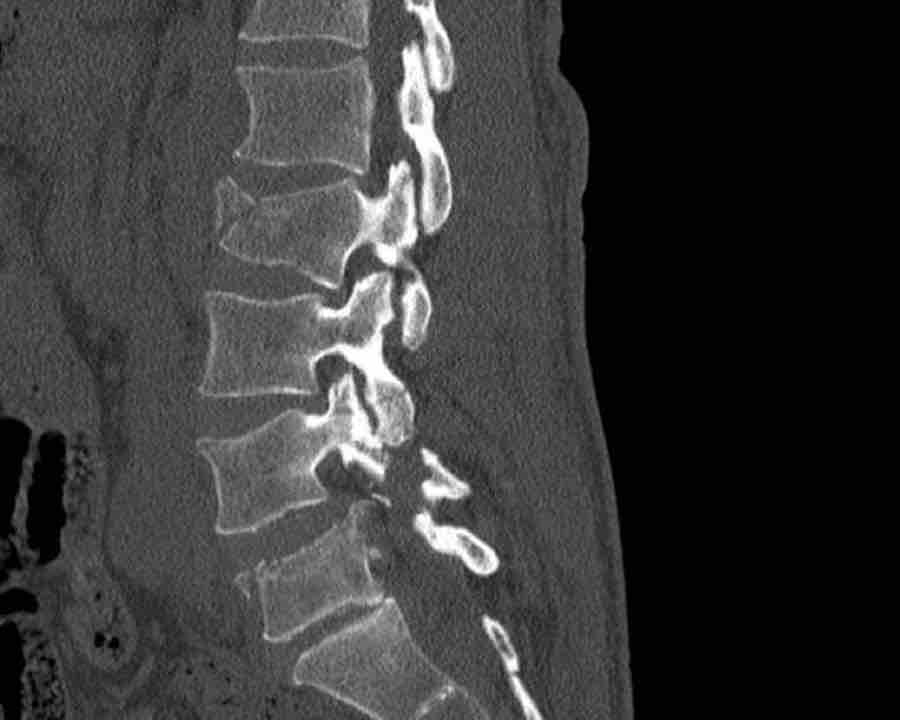

A2 Split fracture

A2 is a fracture of both endplates without involvement of the posterior wall of the vertebral body.

What is the highest AO-type of injury?

Findings:

- No C or B injury

- Fracture of the vertebral body with involvement of both endplates (1+1 points), no posterior wall involvement

Conclusion

injury type A2